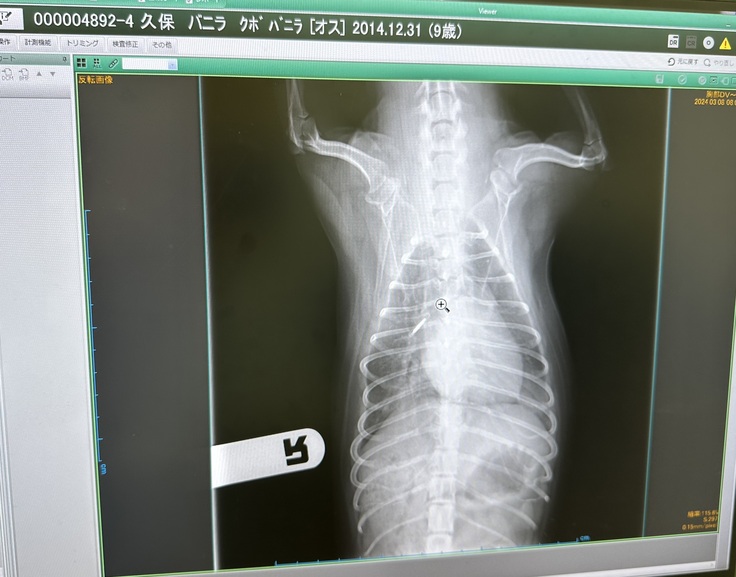

(入院中の肺水腫の画像。本来は黒色です)

主に聴診、レントゲン検査、エコー検査により診断。

肺水腫に罹患した後の生存期間中央値は9か月くらいだそうです。

我が家のバニラは肺水腫で入院中思うように薬が効いてくれず入院期間が延びていました。